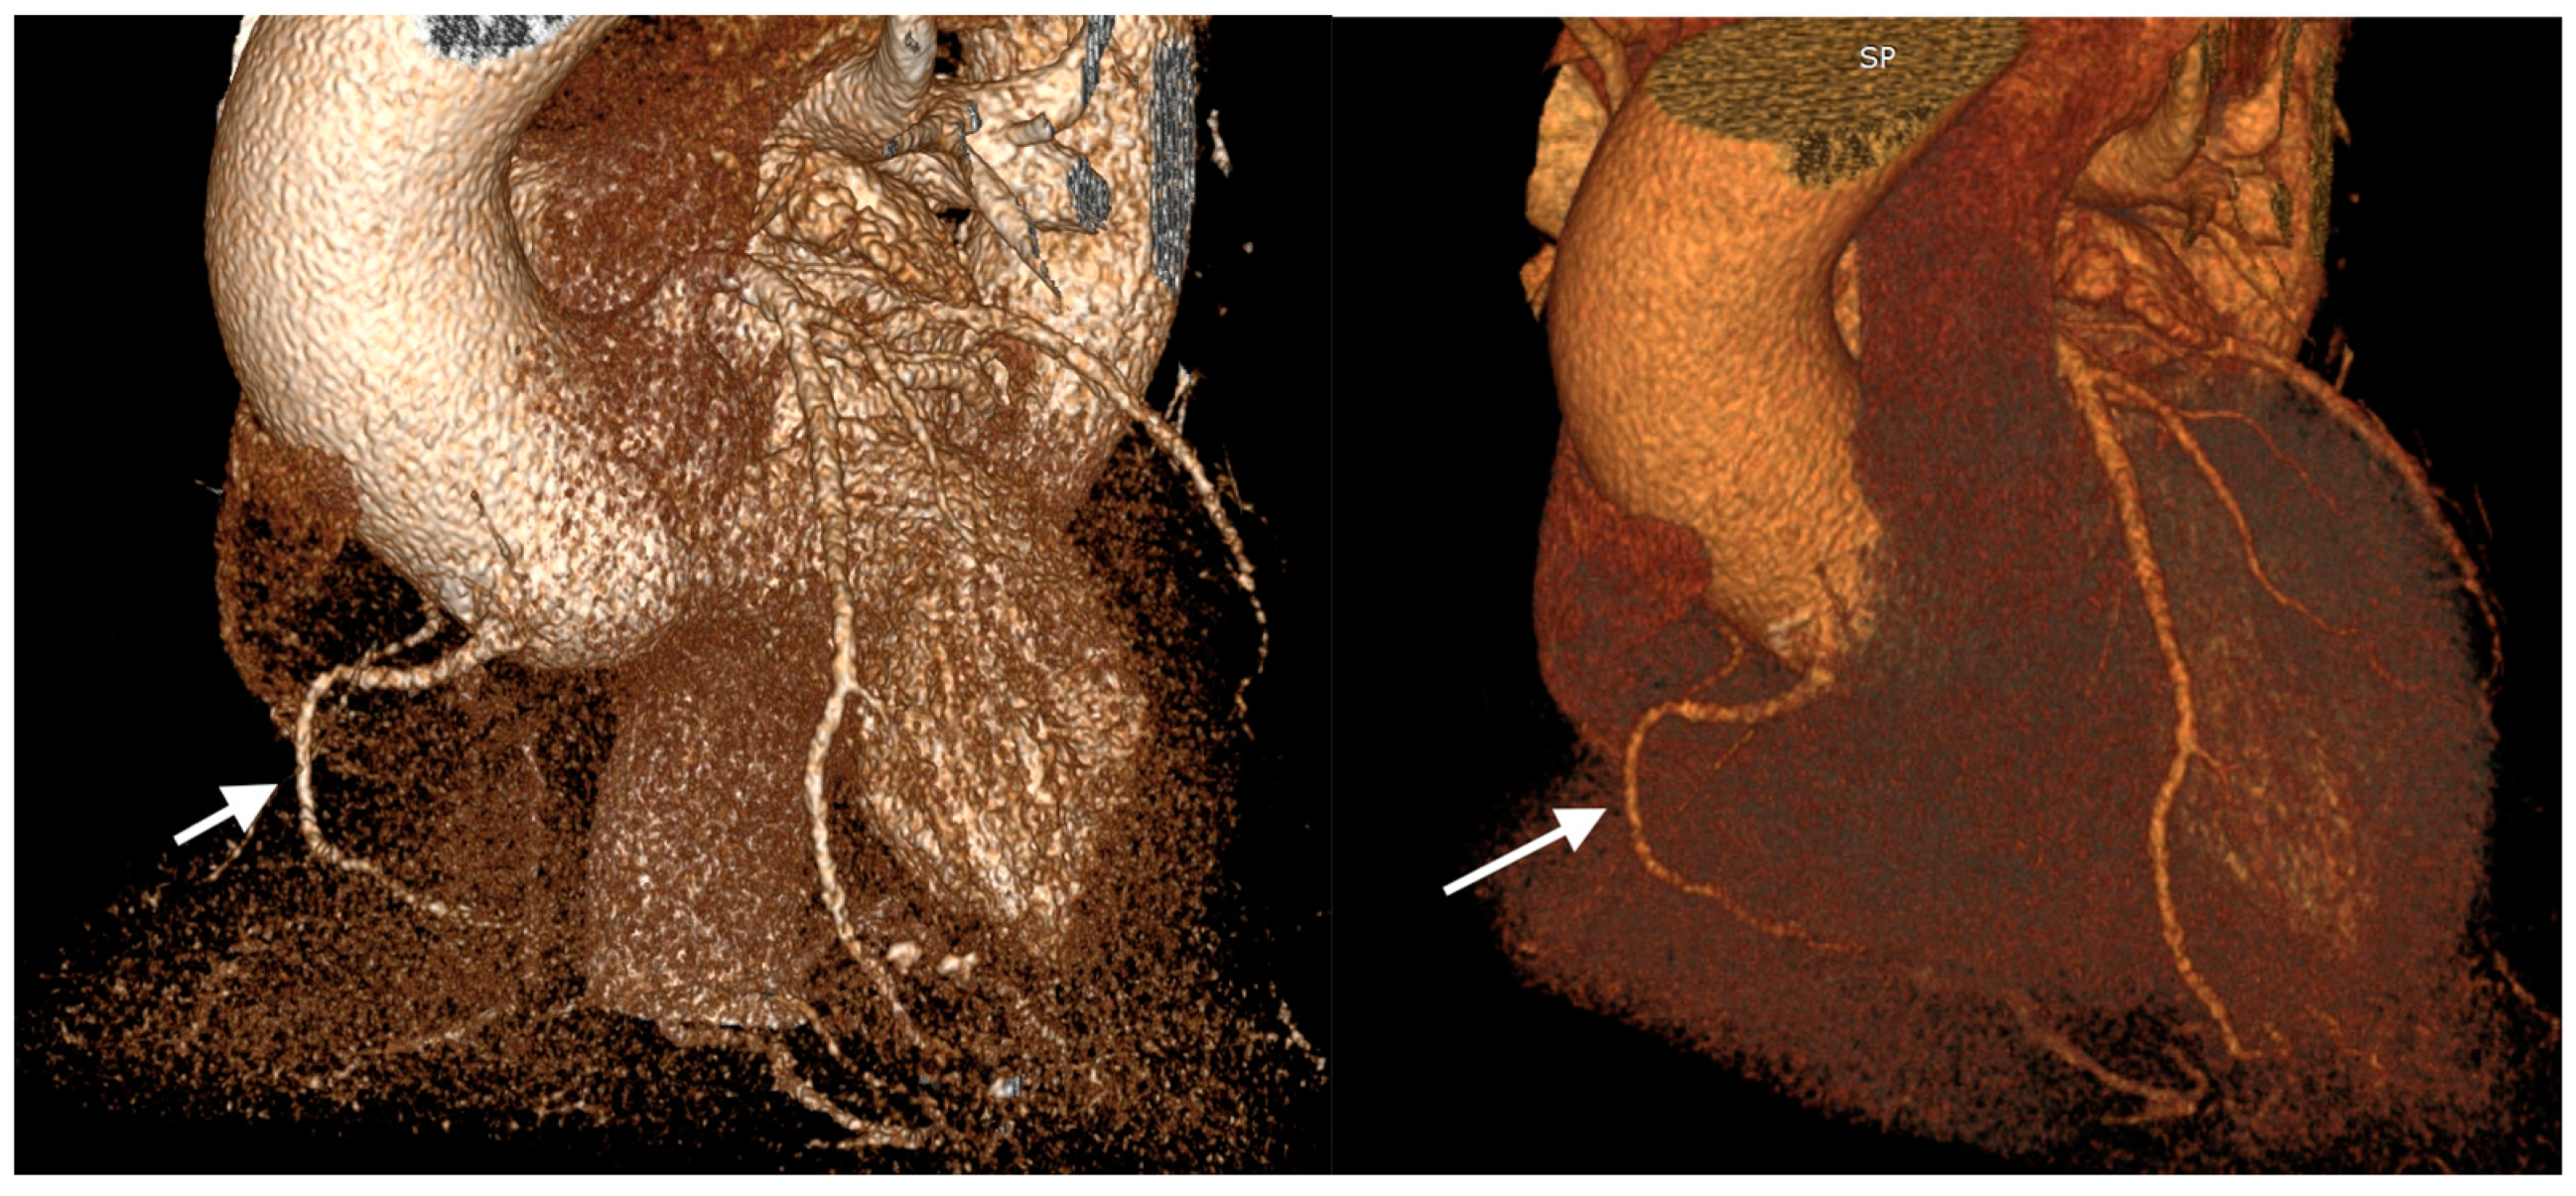

| Coronary artery hypoplasia | 71 | 20.3% | 0.5% |

| Patients (n) | Gender | Hypoplastic Coronary Artery | Stenotic Coronary Artery with Stent Placement |

|---|---|---|---|

| 1 | M | LM | LAD |

| 2 | M | RCA | LAD |

| 3 | F | LAD | LAD |

| 4 | M | LM | LAD |

| 5 | M | RCA | LCx |

| 6 | M | LM | LCx |

| 7 | M | LAD | RCA |